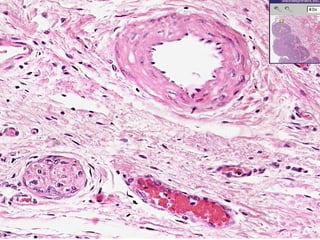

• #10 Classical neurovascular “triad”: Artery, Vein, Nerve

• #11 Smaller neurovascular triad, or “bundle”. How many axons are in this small nerve? Perhaps 5-8?